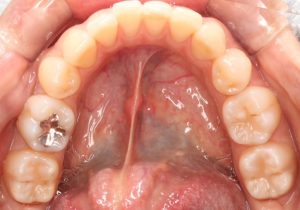

インプラント手術